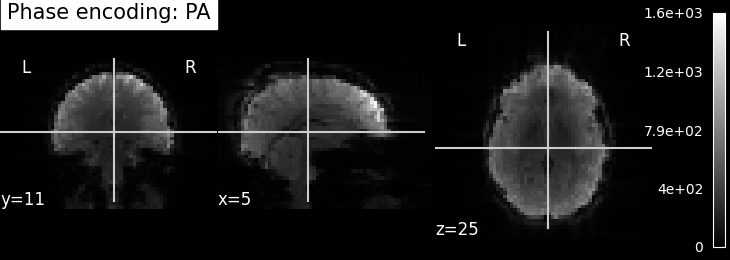

EPI field mapping

EPI images can be utilized to approximate a field map by acquiring two volumes with opposite phase encoding directions. The difference in distortion between these two acquisitions is then utilized in a least squares algorithm to estimate the field map. Although the resulting field map may exhibit some artifacts, as demonstrated in the following images, it is still sufficient to correct for distortion to some extent.

To perform this step, FSL command line tools such as TOPUP, FUGUE, and FLIRT are employed for the analysis. These tools enable the processing and correction of distortion in the EPI images, contributing to improved image quality.